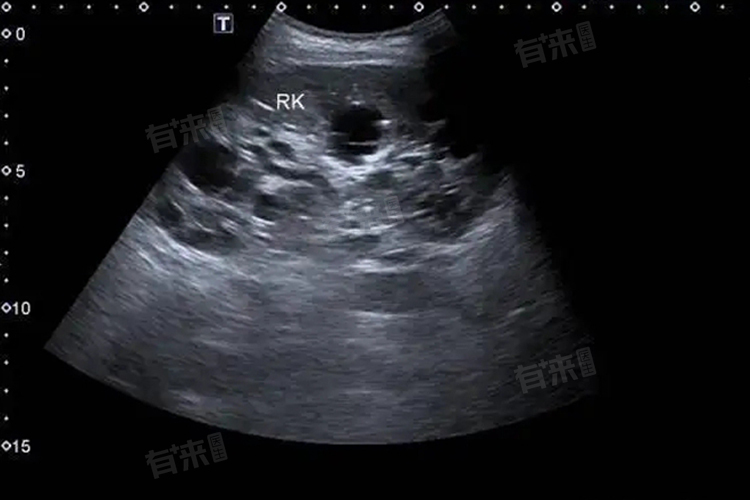

肝实质回声欠均匀是肝脏在超声检查下呈现出的一种表现,提示肝脏可能存在多种病理或生理变化,背后涉及脂肪浸润、纤维组织增生等多方面因素。

当肝脏内脂肪细胞增多,脂肪在肝实质内不均匀分布时,超声下可表现为肝实质回声欠均匀,如在脂肪肝患者中,肝细胞内脂肪堆积,正常的肝组织被脂肪组织替代,由于脂肪与肝实质的声学特性不同,就会出现回声不均匀的情况。轻度的脂肪浸润可能仅表现为局部的回声改变,而重度脂肪肝可能整个肝脏实质回声都呈现不均匀状态。

各种原因导致肝脏纤维组织增生时,也会使肝实质回声不均匀。如慢性肝炎患者,肝脏长期受到炎症刺激,肝细胞受损后机体启动修复机制,纤维组织增生。增生的纤维组织与正常肝实质的回声不同,从而在超声检查中显示为回声欠均匀,在肝纤维化、肝硬化的早期阶段较为常见。

在肝脏肿瘤的早期,当肿瘤组织较小且与周围肝实质的声学差异开始显现时,可能表现为局部的肝实质回声欠均匀。如小的肝血管瘤、肝癌早期等,随着肿瘤的生长,回声不均匀的区域可能会更加明显,并且可能出现其他特征性的超声表现。